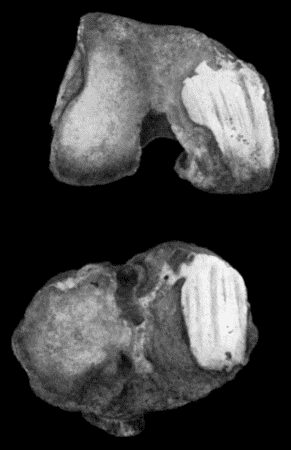

156.Caseating focus in Upper End of Fibula 513

167.Loose Body from Knee-joint 541